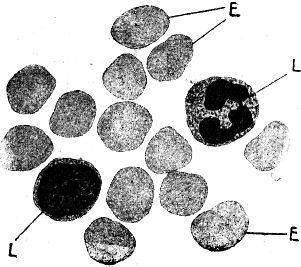

Die ersten Beobachtungen von Bakterien sind gegen Mitte des 17. Jahrhunderts gemacht worden. Der gelehrte Jesuitenpater Athanasius Kircher, wohl der erste Mensch, der lebende Spaltpilze gesehen und beschrieben hat, besaß nur ein recht primitives Vergrößerungsglas, dem man den stolzen Namen Mikroskop heute kaum gönnen würde. Es soll eine 32fache (lineare) Vergrößerung ermöglicht haben, hat also gerade eben nur gestattet, größere Spaltpilze zu sehen. So ist es denn nicht verwunderlich, daß der gelehrte Pater, der ganz richtige Vermutungen über die Existenz kleinster krankheiterregender Lebewesen hegte, zu irrtümlichen Beobachtungen gelangte, da er außerstande war, Bakterien von anderen sehr kleinen Objekten zu unterscheiden. So fand Kircher bei einer im Jahre 1656 in Süditalien herrschenden »Pestseuche« mit Hilfe seines Vergrößerungsglases im Blute der Kranken kleine »Würmchen«, die er als die gesuchten krankheiterregenden Wesen ansprach – gewiß mit Unrecht, denn er hat wahrscheinlich nichts anderes gesehen als die sogenannten roten Blutkörperchen, kleine Scheibchen, die in unserem Blute immer vorhanden sind und einen seiner wichtigsten Bestandteile bilden. Athanasius Kircher war eben ganz auf dem richtigen Wege zum Ziele, aber mit seinen mangelhaften Hilfsmitteln konnte er es nicht erreichen.